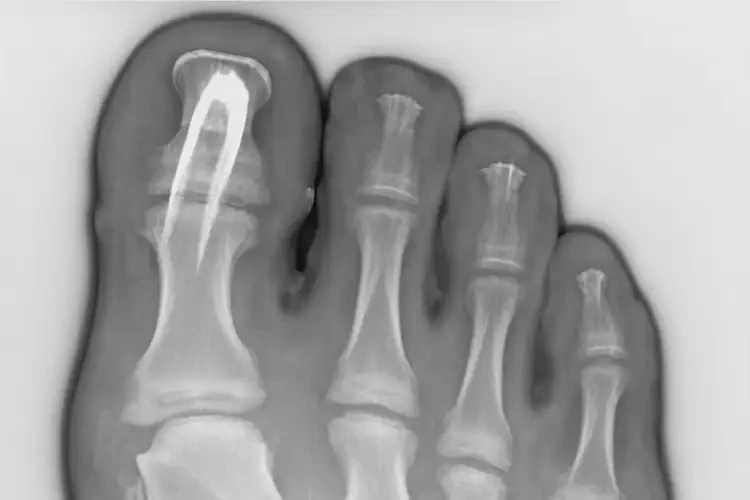

3. 骨刺:足跟骨刺是足跟疼的另一個(gè)常見原因,通常與年齡和關(guān)節(jié)退化有關(guān)。

遼寧阜新康復(fù)科看足跟疼要多久(圖1)